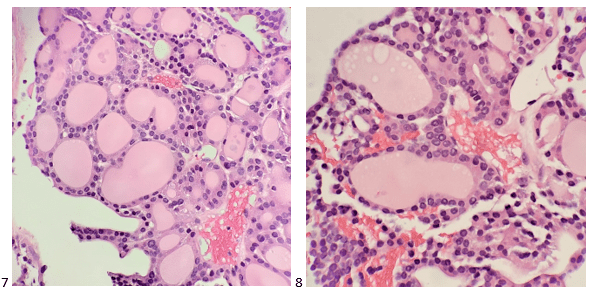

A 58-year-old male presented with multiple lung nodules and a brain mass. We reviewed the brain mass excision from an outside institution and agreed with the original diagnosis of anaplastic oligodendroglioma, WHO grade III with a Ki-67 proliferation index that approached 20%. EGFR was not amplified (ratio 1.2), but 1p/q19 co-deletions were noted in greater than 75% of tumor cells. To rule out primary versus metastatic disease, the patient had a CT scan-guided biopsy of right upper lobe lung mass. No malignant cells were identified in the sample; however, necrotic debris and abundant fungal hyphae were noted (Images 7-9). A portion of the sample was sent to Microbiology for culture. The following day, a GMS and PAS stains were performed on paraffin-embedded sections of the cell block which demonstrated the same fungal hyphae seen in the smears and cell block preparations (Images 10 & 11).

Diagnosis: Abundant fungal hyphae, consistent with Aspergillus